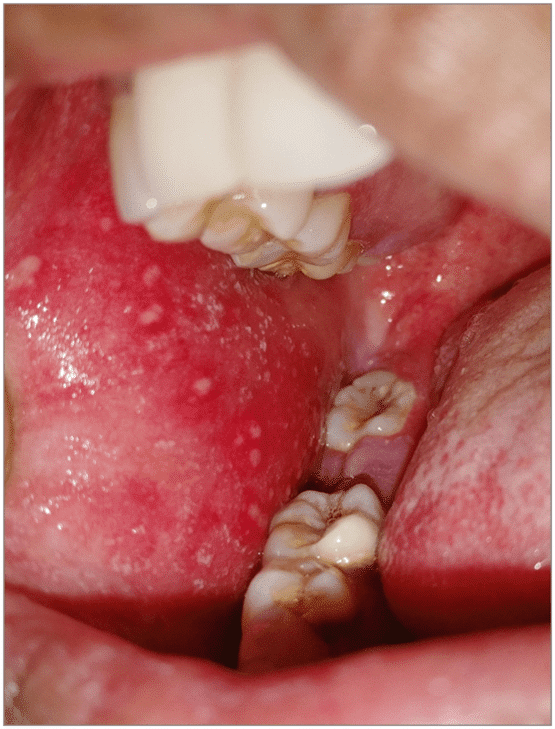

Koplik spots observed on the buccal mucosa

It is characterized by an onset of high-grade fever that lasts 4 to 7 days after exposure, malaise, cough, coryza, and conjunctivitis – the three “C’s.” Koplik spots (white spots on the buccal mucosa) and a maculopapular rash appear after a few days of exposure.